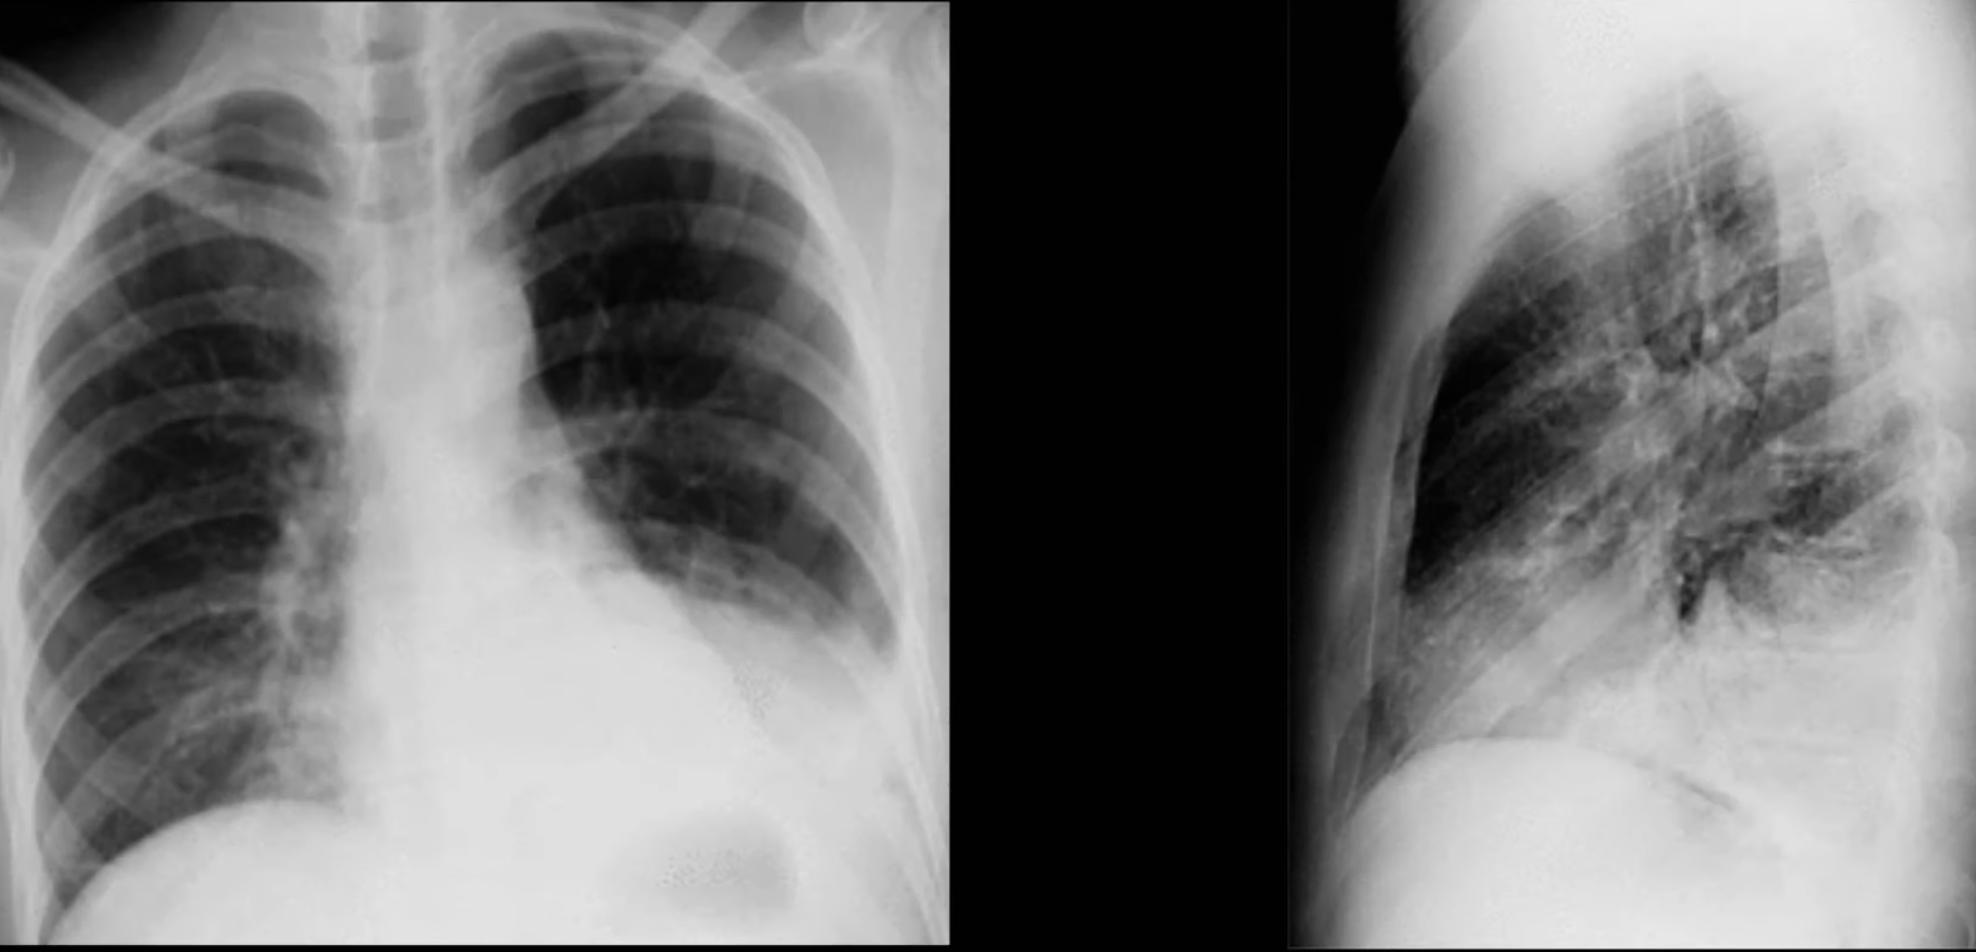

Pleural Effusion

Small effusions are often first visible on the lateral film before the AP.

Subpulmonic Effusion

Fluid accumulation between the lung base and the diaphragm, not tracking up the pleura and therefore not blunting the costophrenic angle.

Suggested by:

- Diaphragm appears to peak more laterally than normal

- Diaphragm appears more horizontal than normal

- On left: abnormally large distance between gastric bubble and lung base

- On right: abnormally high horizontal fissure